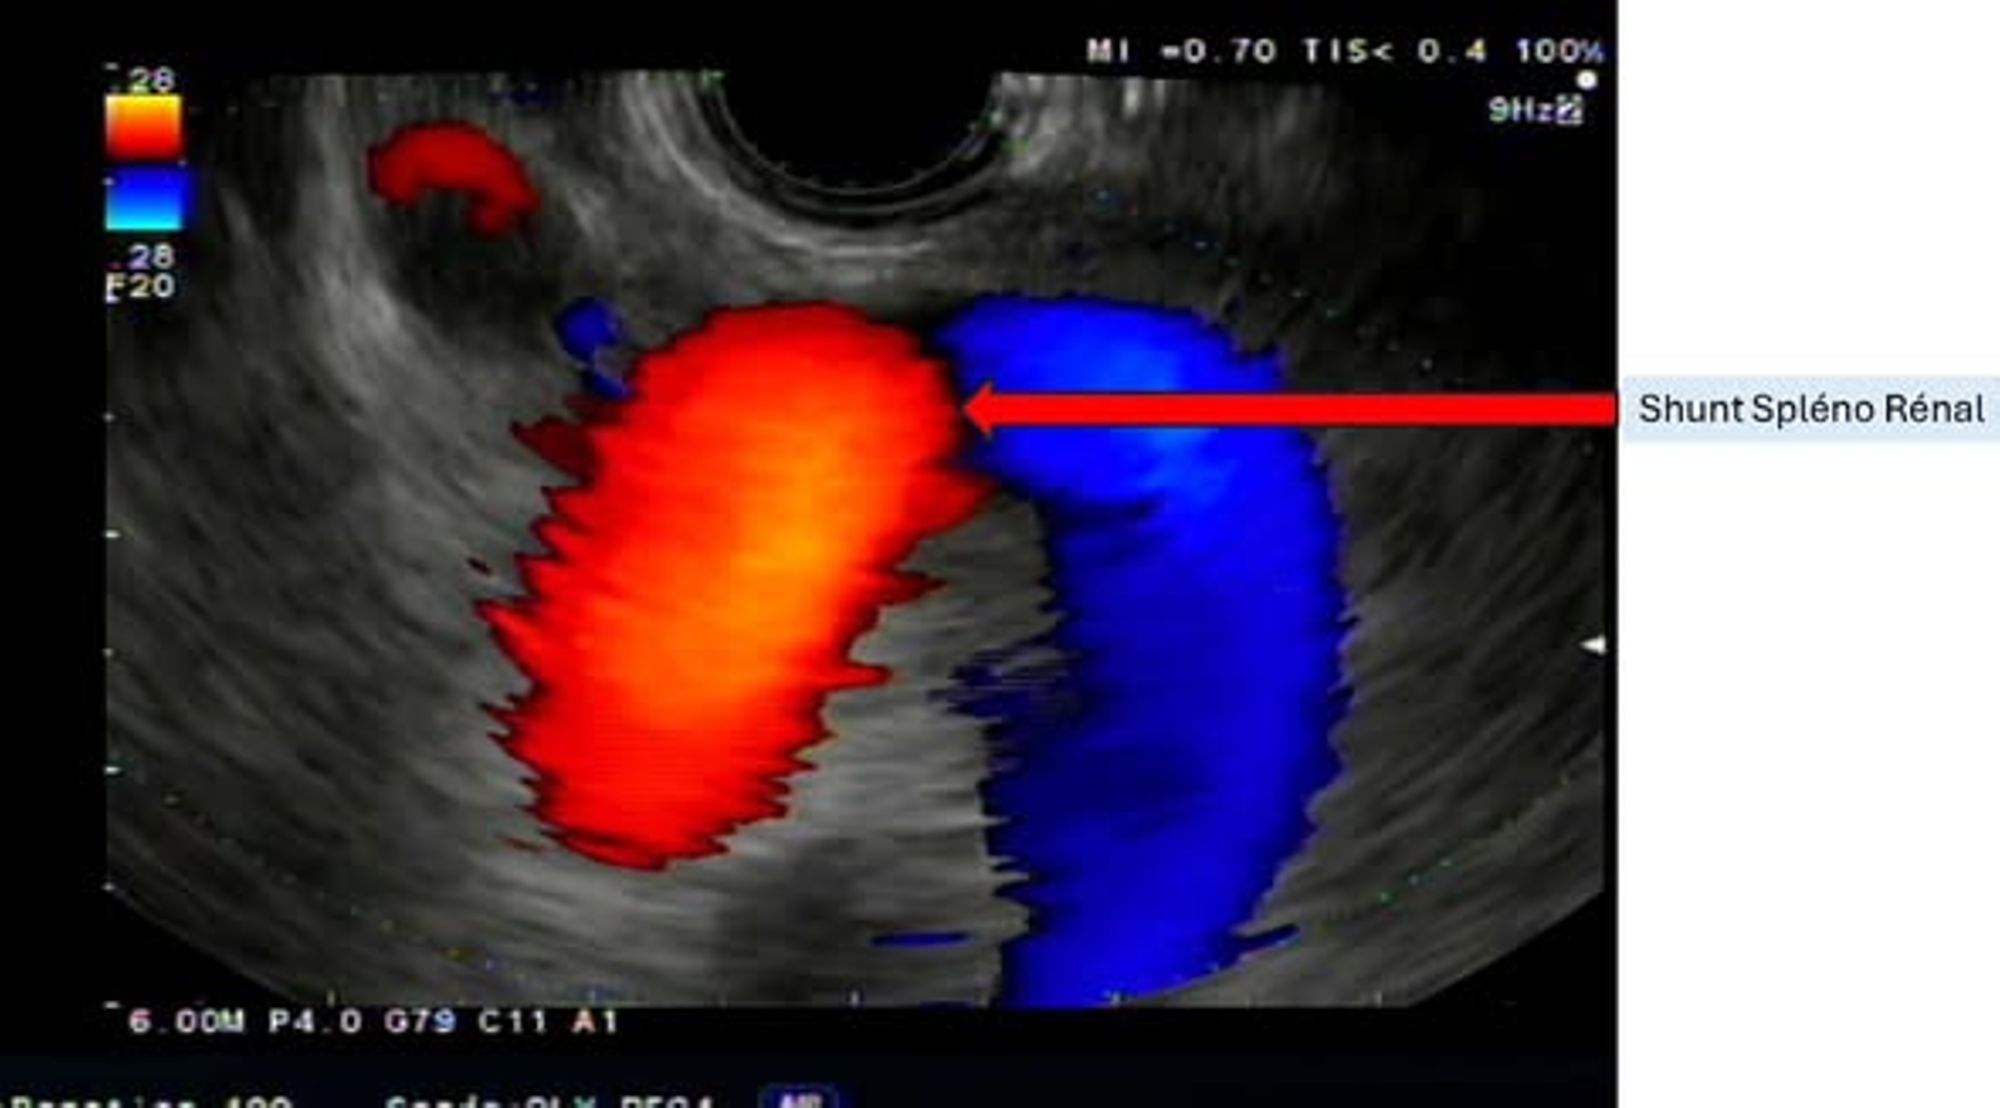

Chez certains patients, cette situation est aggravée par l’existence de « courts-circuits » naturels entre les vaisseaux sanguins, appelés shunts, qui permettent au sang de contourner le foie et d’envoyer directement les toxines vers le cerveau.

À l’hôpital Saint-Joseph, le Dr Paul CASTELLANI a réalisé l’embolisation par écho-endoscopie de ce shunt chez un patient souffrant d’une maladie grave du foie compliquée d’épisodes répétés et invalidants d’encéphalopathie hépatique.

Grâce à cette méthode, le médecin a pu intervenir pour atteindre directement les vaisseaux responsables du court-circuit et l’obstruer à l’aide de petits ressorts métalliques appelés coils et d’une colle biologique, afin de bloquer totalement le passage anormal du sang. L’intervention s’est déroulée sans complication, lors d’un examen d’écho-endoscopie classique, sous anesthésie générale. À ce jour, cette procédure réalisée par voie écho-endoscopique est considérée comme une première en Europe.